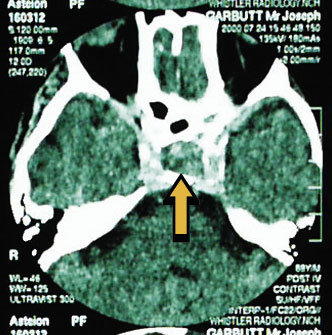

A presumptive diagnosis of pituitary apoplexy was made, and the patient was commenced immediately on intravenous fluids and hydrocortisone 100 mg, 12-hourly. The CT scan (Box, B) confirmed the diagnosis, showing a pituitary tumour measuring 12 mm in diameter. The salient feature is the variegated appearance, suggesting haemorrhage within the tumour.

This picture of the patient's eyes 12 hours after commencing hydrocortisone (A) shows partial left third cranial nerve palsy and complete right third cranial nerve palsy. A computed tomographic image (B) shows a 12 mm diameter pituitary tumour with haemorrhage (arrow). The mechanism of third cranial nerve palsy is illustrated in C: as the tumour expands, it involves the optic chiasm anteriorly and displaces the carotid siphon laterally. The third cranial nerve is vulnerable to lateral displacement. (Adapted from Patten J. Neurological differential diagnosis. New York: Springer Verlag, 1982.)